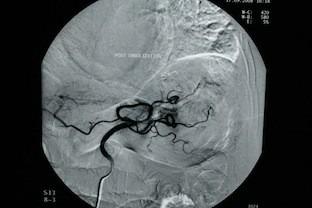

针对源自胃血管发育异常的大量上消化道出血进行选择性栓塞治疗。

Selective embolization for massive upper gastrointestinal bleeding deriving from gastric angiodysplasia.

Transcatheter arterial embolization is a valuable, minimally invasive method, used as treatment for upper gastrointestinal bleeding, after failed primary endoscopic approach. It is a safe and effective procedure, but it's use is limited because of relatively high rates of rebleeding and mortality. The aim of this paper is to present a case of severe, massive upper gastrointestinal bleeding deriving from gastric angiodysplasia, which was treated successfully with superselective embolization. The patient recovered from the haemorrhagic shock and avoided emergency surgical intervention.

经导管动脉栓塞术是一种有价值的微创方法,用于在初次内镜治疗失败后治疗上消化道出血。它是一种安全有效的手术,但由于再出血和死亡率相对较高,其应用受到限制。本文的目的是介绍一例因胃血管发育异常导致的严重大量上消化道出血病例,该病例通过超选择性栓塞术成功治疗。患者从失血性休克中康复,避免了紧急手术干预。